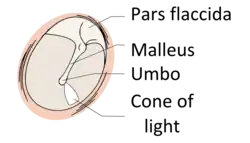

Schema eines unauffälligen otoskopischen Befundes. Rechtes Trommelfell in der Ansicht von lateral. Hellgrau Pars flaccida des Trommelfells und Manubrium des Hammers (Malleus), dunkelgrau Pars tensa des Trommelfells mit Lichtreflex, (hier cone of light), rosa Trommelfellrand, Anulus fibrocartilagineus

Hierbei sind die histologisch verschiedenen Trommelfellabschnitte mit zu berücksichtigen. Die kleine Pars flaccida oder auch Shrapnell’sche Membran besteht aus nur zwei Schichten; zum äußeren Gehörgang hin findet sich ein mehrschichtiges Plattenepithel, Stratum cutaneum, während zur Paukenhöhle hin ein einschichtiges Plattenepithel, Stratum mucosum ausgebildet ist. Zwischen den beiden unterschiedlichen Zellschichten liegt nur die Basallamina. Anders bei der größeren Pars tensa: Hier sind ebenfalls die beiden Zellschichten und die Basallamina ausgebildet, aber zusätzlich lassen sich noch zwei bindegewebige Faserschichten, Stratum fibrosum oder Lamina propria, unterscheiden. Eine dieser Faserschichten hat einen radiären Verlauf, Stratum radiatum, und die andere ist zirkulär angeordnet, Stratum circulare.

Die Diagnose wird mit Hilfe der Ohrmikroskopie gestellt. Der typische Befund ist ein Defekt in der Pars tensa oder Pars flaccida des Trommelfells mit Nachweis weißlich-gelber Schuppen oder Zellmassen in der Läsion. Nicht selten finden sich Polypen aus Granulationsgewebe. Untersucht man das Trommelfell durch die direkte Otoskopie, sieht man häufig eine Perforation des Trommelfells am oberen oder hinteren Rand.